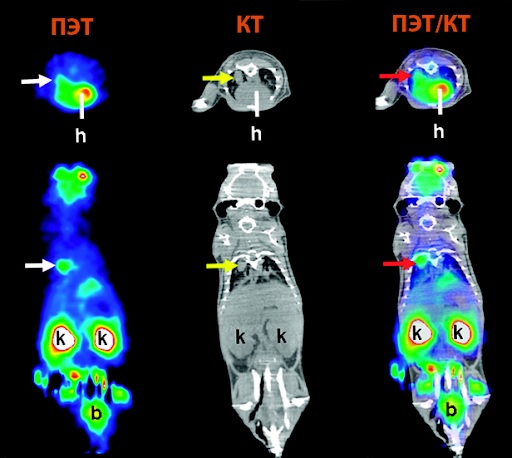

Если речь идет о травмах и болезнях плотных структур, то пациентам назначают компьютерную томографию и ПЭТ КТ, причем КТ тоже может проводиться с введением контрастного вещества. В первом случае рентгенолог изучает анатомические особенности органов и тканей, при необходимости используя усиливающие сигнал препараты, а во втором – определяет отклонения в динамике, исследуя функциональную активность. Позитронно-эмиссионная томография считается наиболее прогрессивным методом и дает больше информации, чем КТ с контрастом. К недостаткам обследования можно отнести его длительность (причем пациент должен сохранять неподвижность в течение всей диагностики) и высокую стоимость.